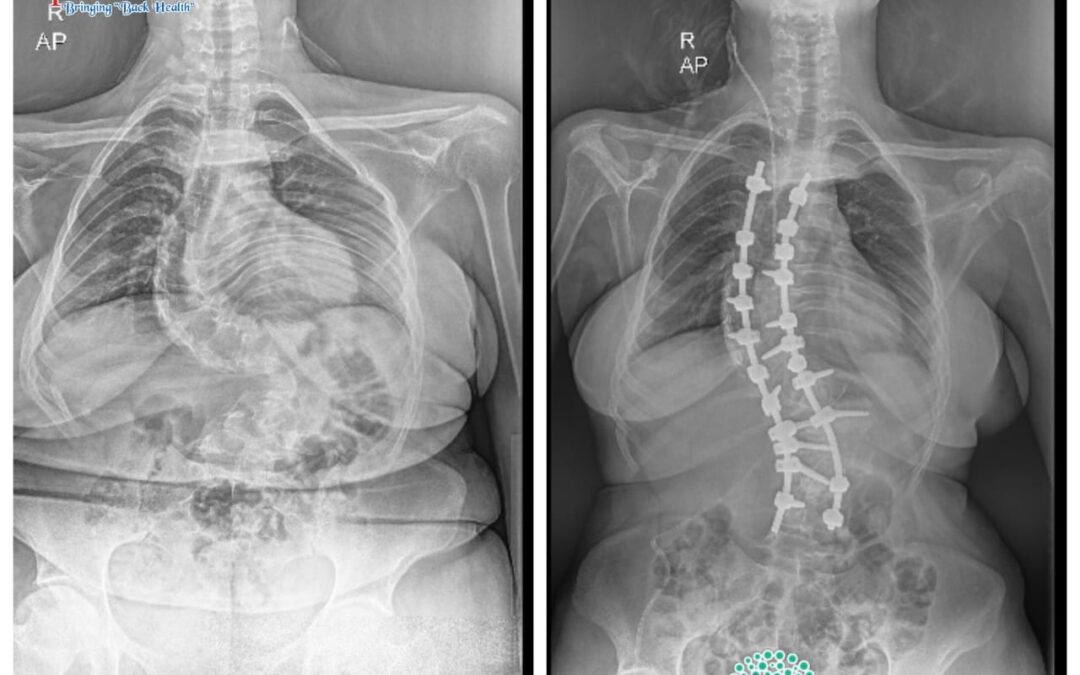

‘Bringing back Curves as Smile’ in a 19 year Scoliosis girl

19/F Ms. Pretty complained to Dr. Ramachandran of her shoulder and waist asymmetry as well as back pain. She...